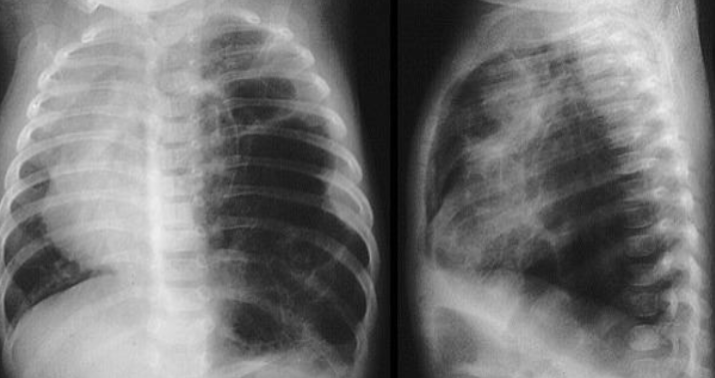

- Anterio-posterior [AP] chest radiograph shows multiple cystic lesions inâ (1 -the middle and lower zones of the left hemi-thorax with ill-defined left hemi diaphragm. There is mediastinal shift toward the right. These lesions are -bowel loops inside the left hemi-thorax. The film is over exposed (over .(penetration

- The diagnosis is Left Sided Congenital Diaphragmatic Hernia (CDH). This - (2 is called bockdalic CDH. CDH is usually in the left side (90 %). The defect is found in the posterio-lateral aspect of the diaphragm. CDH is associated with .lungs hypoplasia in the same side and to a lesser extent in the opposite side .This may be complicated by pulmonary hypertension and severe hypoxemia

- The treatment of CDH is immediate endo-tracheal incubation if it is - (3 diagnosed in-utero or if it is highly suspected after birth (with following symptoms and; respiratory distress (RD), cyanosis, asymmetrical chest movement, bowel sounds heard in the chest and scaphoid abdomen). After intubation, the patients is put on mechanical ventilator and the pulmonary hypertension [PH] is controlled and hypoxemia is reversed. PH and severe hypoxemia may require inhaled Nitric Oxide [iNO], High frequency Oscillatory Ventilation [HFOV] and Exogenous Surfactant administration through endotracheal tube [ETT]. After the stabilization of the arterial blood gases the patient is taken to suture the defect. If the defect is large, a mesh,[ABGs] device may be used. The most important differential diagnosis is Cystic .Adenomatoid Malformation [CAM]